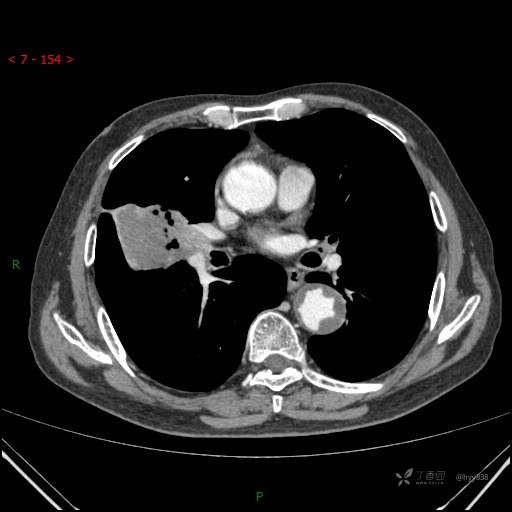

增强动脉期

静脉期